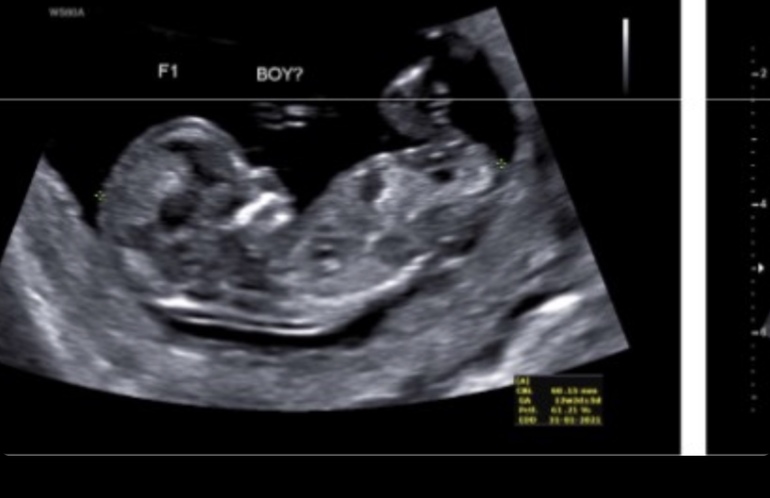

По старшему срок 13+1. Но вот если в пятницу нам предположил супер спец двух девочек, сегодня предполагают уже мальчика и девочку.

Понятно, что на таком сроке рано, но кто тут понимает по картинкам?) поможете мне?)

Вот мальчик типа

Вот да) там как по учебнику половой бугорок) а сверху мне на яички похоже, но это же наверняка не они)))